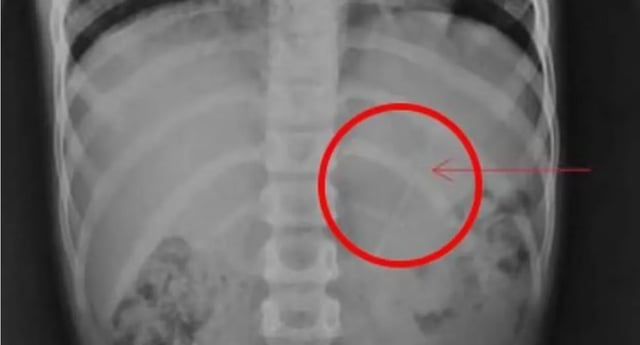

محمد الرخا - دبي - السبت 18 مايو 2024 03:03 مساءً - نجا طفل نيبالي يبلغ من العمر 7 أعوام، بعد أن ابتلع قلم رصاص بطول 10 سنتمترات استقر في معدته، بحسب فحوصات الأشعة السينية لصدر الصبي وبطنه.

صورة لقلم الرصاص الذي استقر في معدة الطفلمتداولة